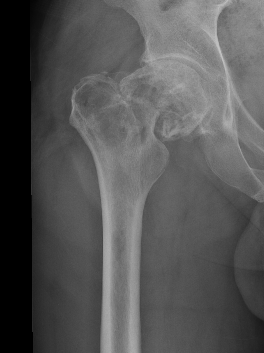

- proximal femur

Lytic lesion with punctate or spotty calcification

Worrisome features

- growth over time

- large > 5cm

- endosteal scalloping is hallmark of chondrosarcoma